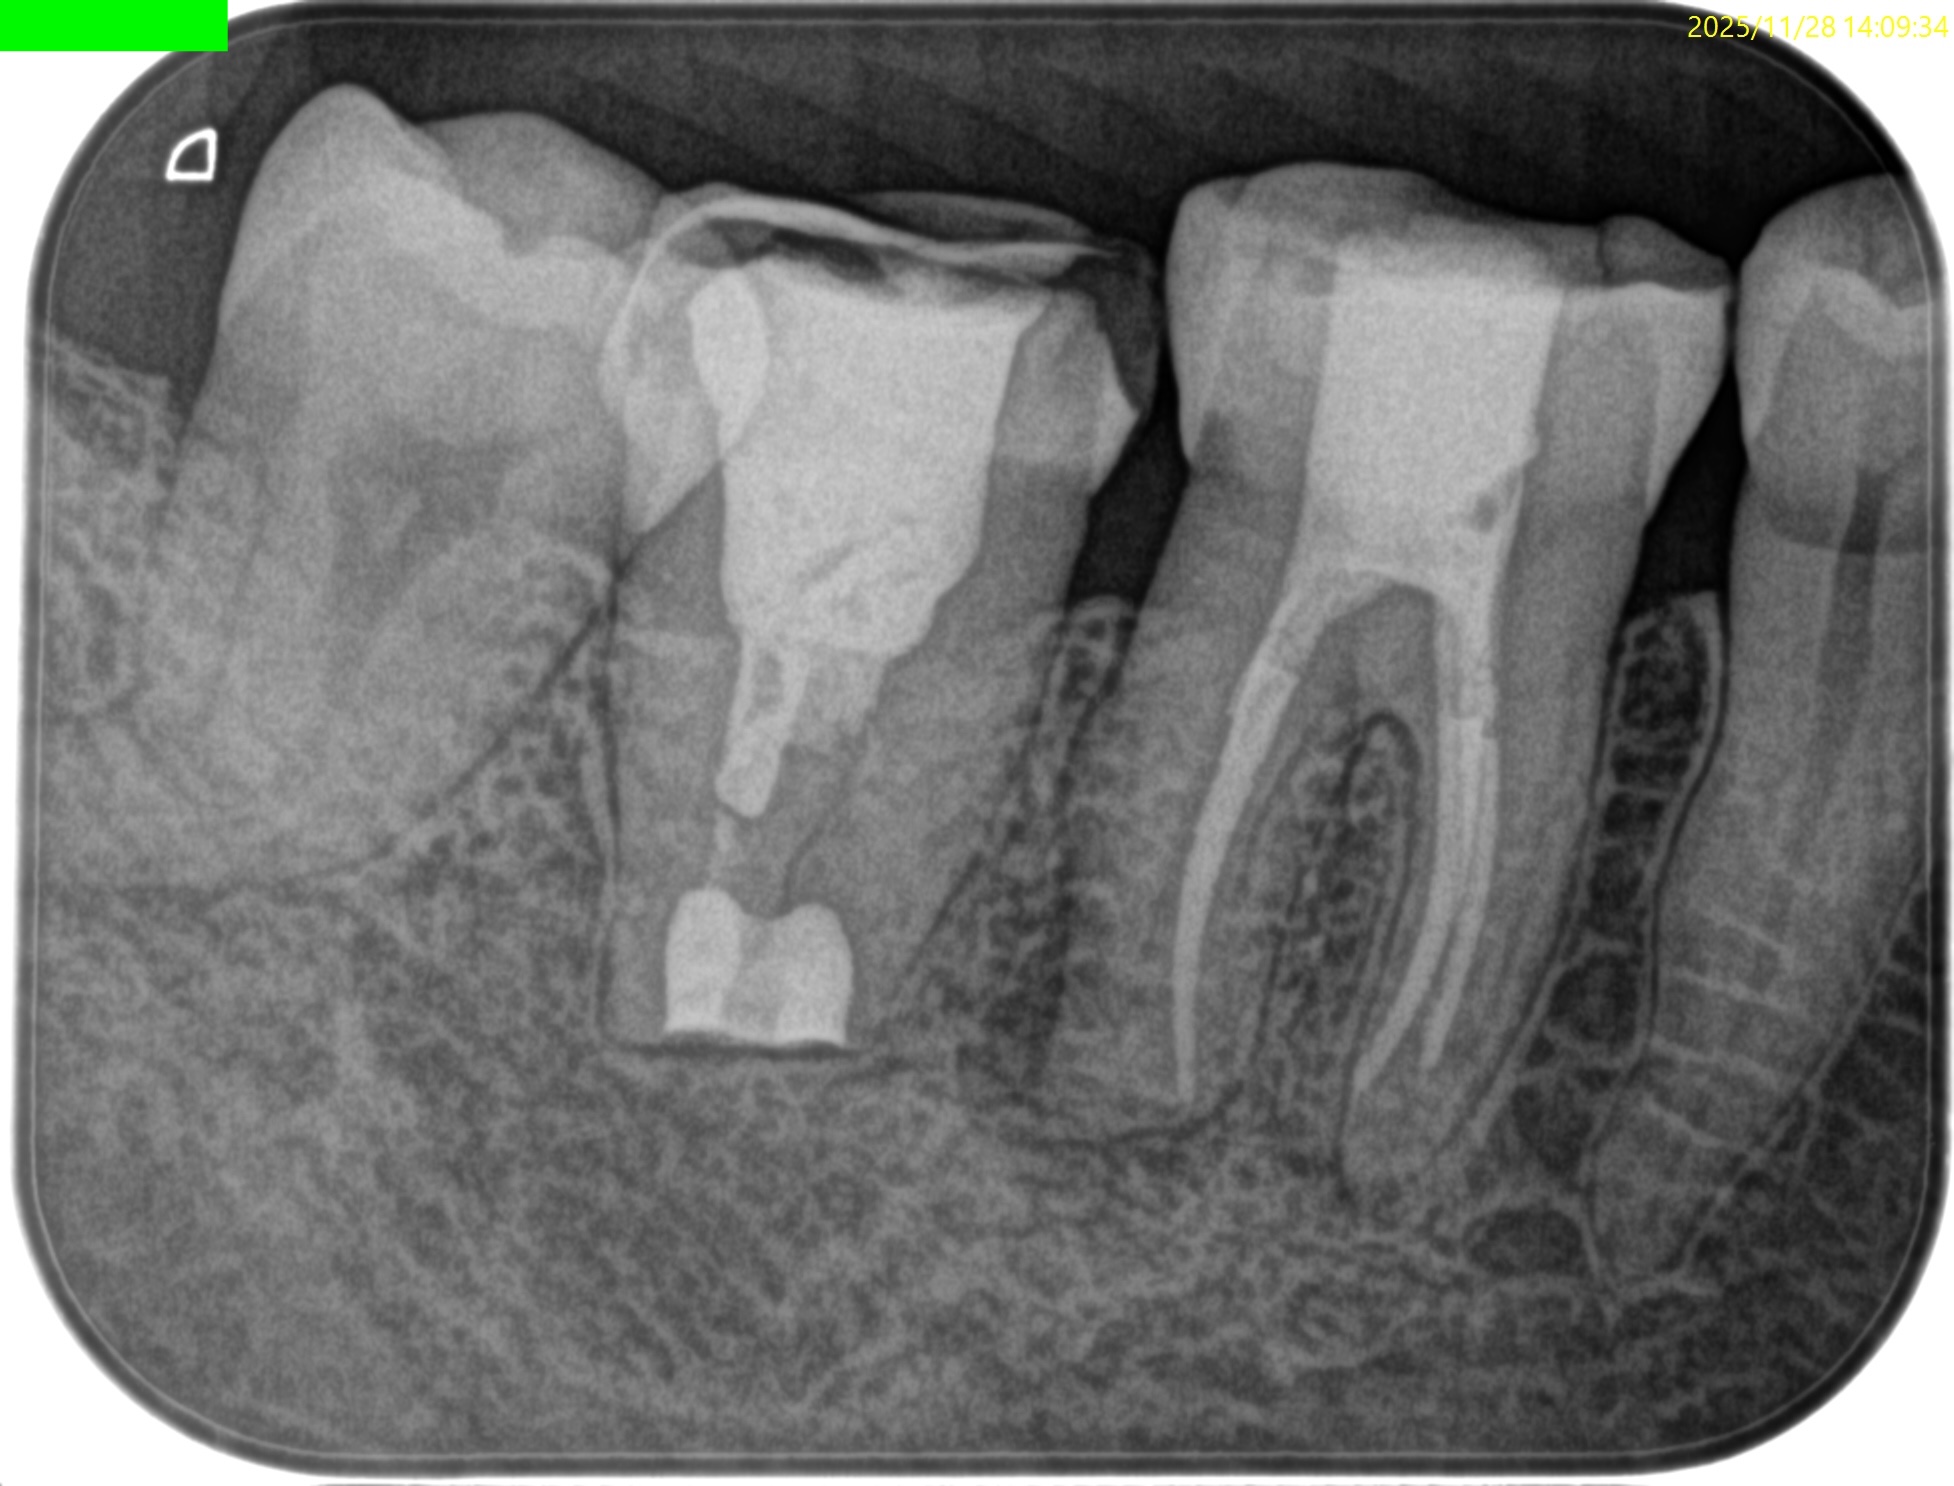

#31 Intentional Replantation 1yr recall(2025.11.28)

初診時と比較した。

劇的に治癒していることがわかる。